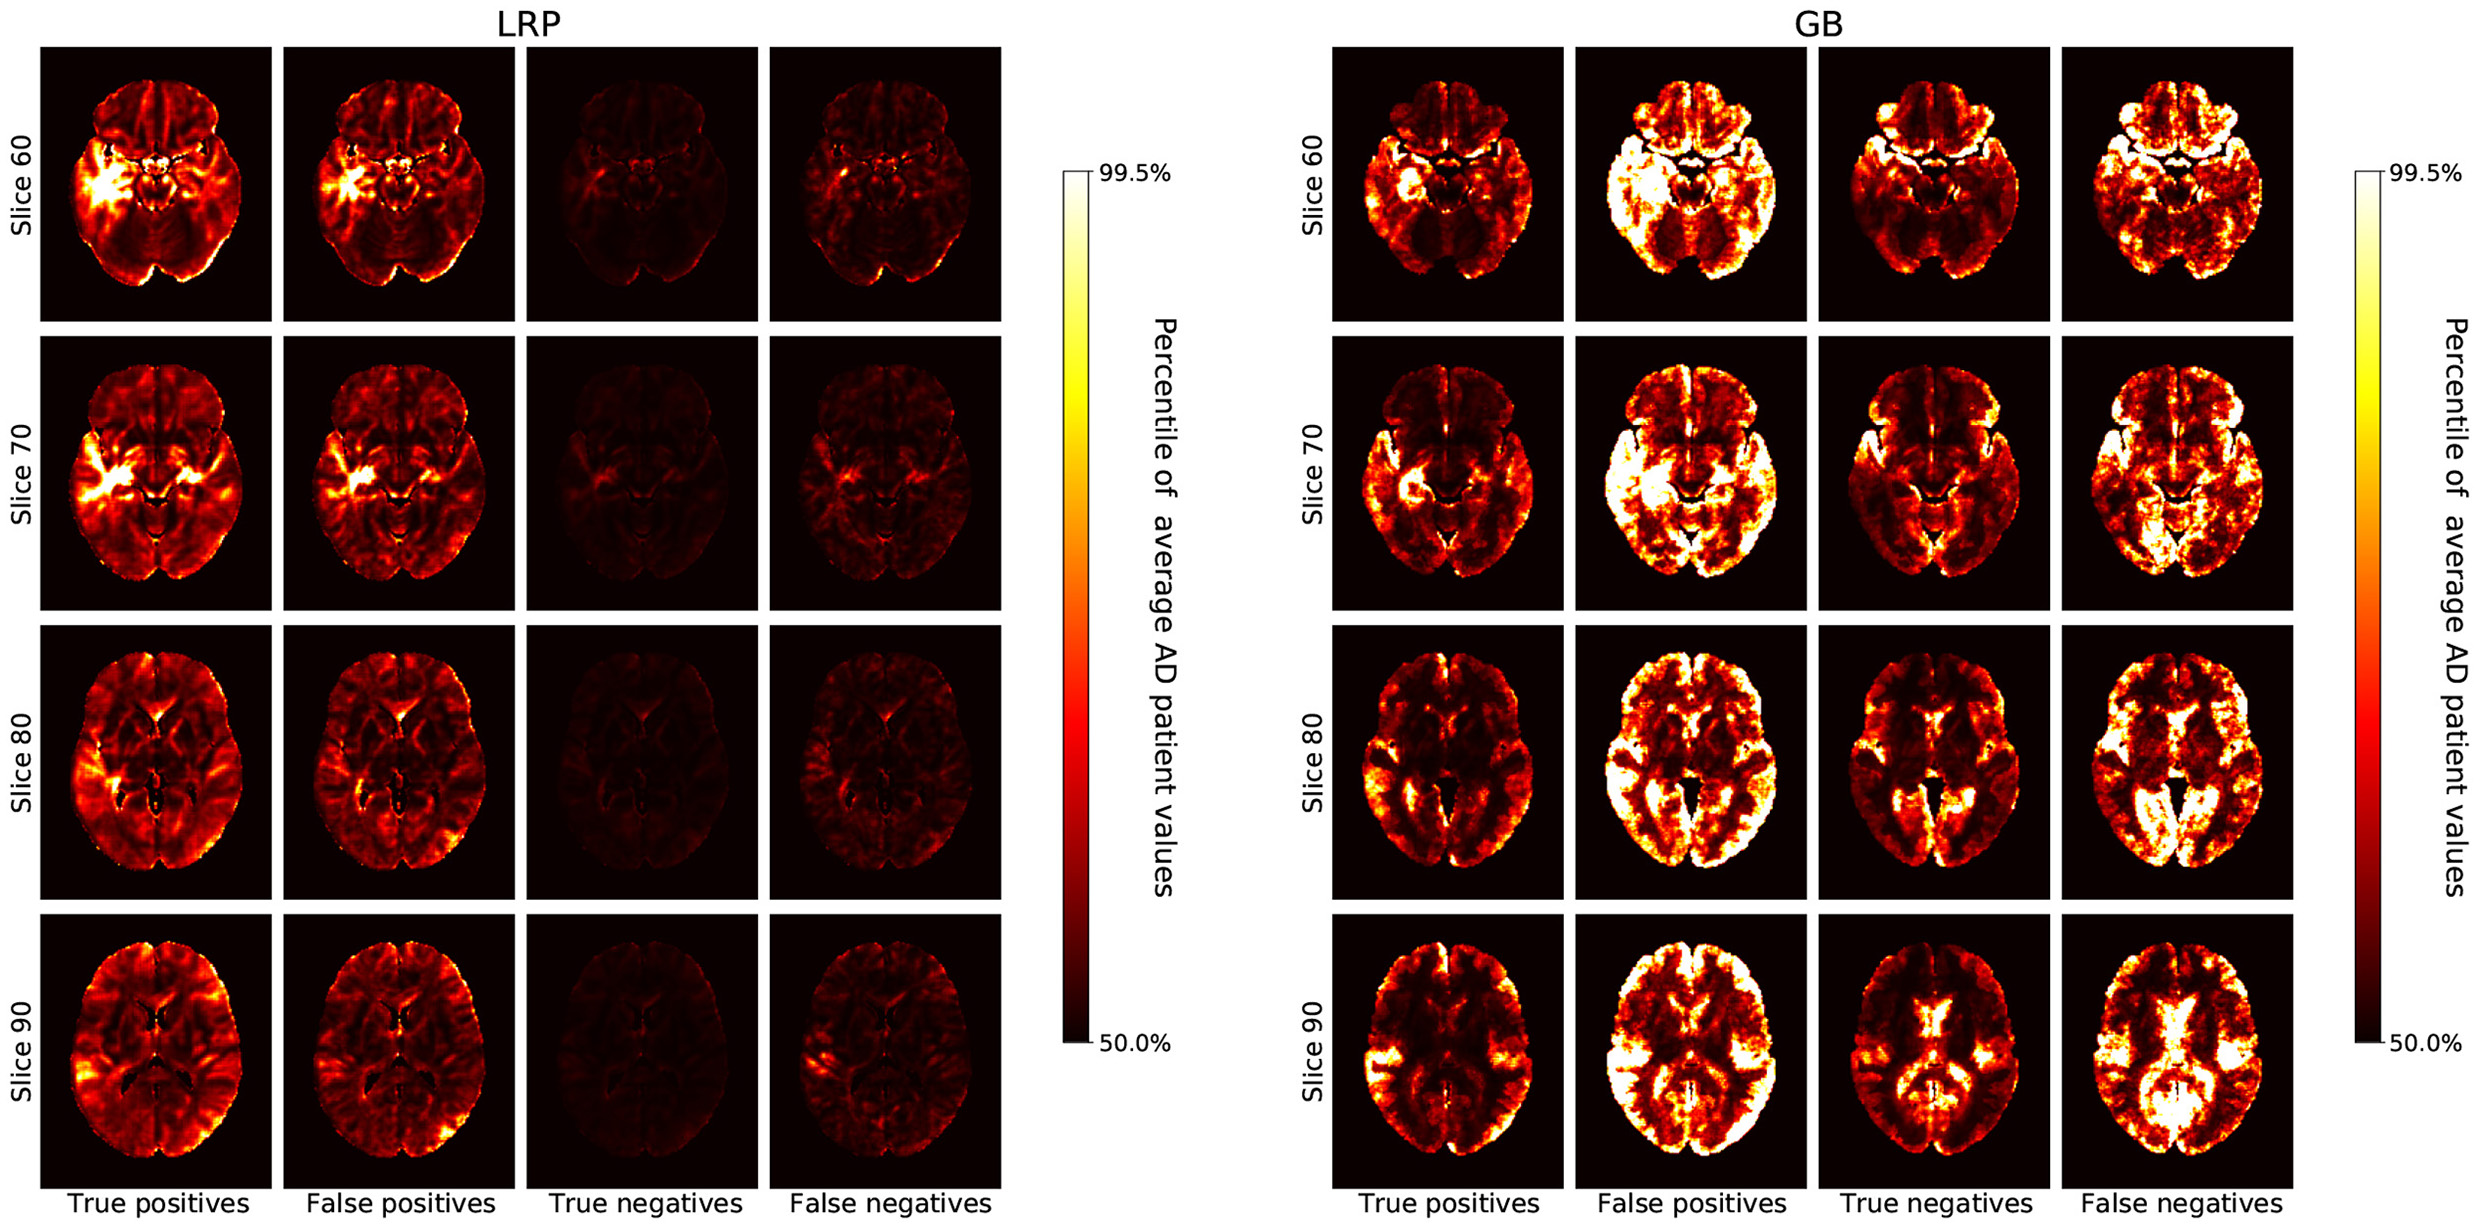

Figure 3

The average heatmaps over all subjects in the test set are plotted for the following cases (Left to Right): true positives, false positives, true negatives, and false negatives; separately for LRP with β = 0 (Left) and GB (Right). For each heatmap, the color-coding is the same as in Figure 2, i.e., with all values smaller than the 50th percentile of the average AD patient in black, increasing values going over red to yellow, and all values greater than the 99.5th percentile in white.

In Figure 3, we show the average heatmaps for the distinct classification cases (true positives, false positives etc.), separately for LRP (β = 0) and GB. In particular, the false positives lead to an interesting insight: For LRP, the false positives exhibit less relevance than the true positives, but generally in similar areas. This could indicate that in these patients structures that are correlated with AD were found, albeit that overall the positive contribution was less compelling than for true AD patients. For GB, on the other hand, the false classifications (mostly false positives, but also false negatives) seem to exhibit the highest gradient values of all cases. This exemplifies well what GB truly measures: in the case of false positives (and negatives), the network might be “unsure” and more easily influenced to change its decision; the outcome is unstable. The highlighted areas that could change the outcome are very broadly distributed and need not necessarily represent areas with positive contributions for AD.